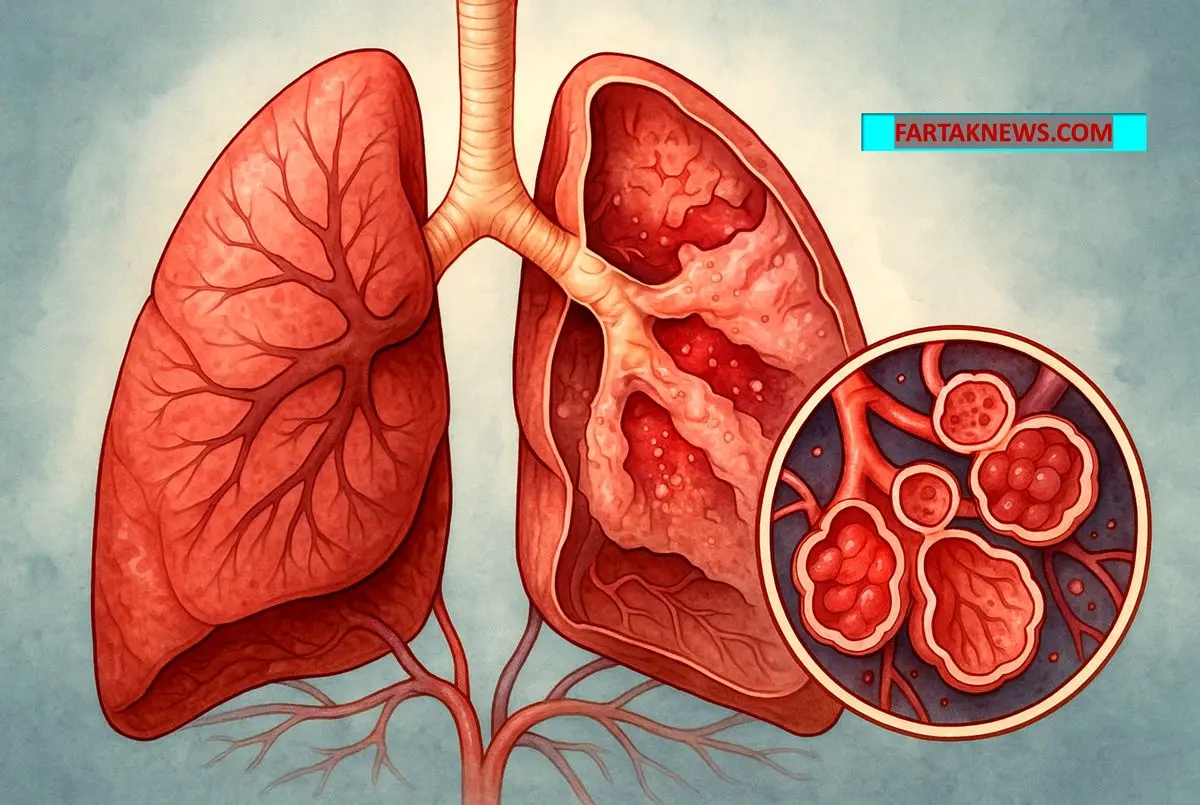

ARDS یک اختلال تنفسی خطرناک است که در آن ریهها بهدلیل التهاب شدید و پر شدن آلوئولها از مایع، توان رساندن اکسیژن به بدن را از دست میدهند و بیمار نیاز فوری به مراقبتهای ویژه دارد.

در ARDS کیسههای هوایی ریه به دلیل التهاب گسترده و آسیب واردشده، از مایع پر میشوند. این تجمع مایع مانع تبادل طبیعی اکسیژن و دیاکسید کربن میشود و فرد بهسرعت دچار کمبود اکسیژن میگردد. همین مسئله است که این وضعیت را به یکی از خطرناکترین اختلالات تنفسی تبدیل میکند.